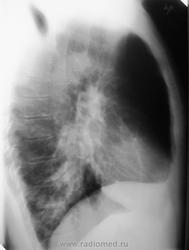

Неоднородная инфильтрация базальных сегментов нижней доли правого лёгкого. Правый корень неструктурен.

Нужна какая-нибудь клиника, но считаю, что на пневмонию похоже (взгляд врача-интерна))

Ателектаз н/доли правого легкого. Показано бронхологическое исследование

Согласен. Необходимо исключить центральный процесс НДБ.

Вот и мне не понравилась "инфильтрация". Да и верхний этаж переднего средостения тоже, но на моих репродукциях © плохо это видно. Врач (ВОП) по телефону заверила, что клинически ОРЗ или пневмония. Очень удивилась, что может и не только пневмония. Так что жду на контроль после противовоспалительной терапии (с амбулаторной картой!)). Появится - отпишусь.

Всё таки интенсивная неоднородная инфильтрация в базальных сегментах с распадом.На онко не смахивает.

Пока - на первом месте сливная пнвмоническая инфильтрация в 7 и 10 сегментах, и полечить нужно как пневмонию. Ателектаза всей доли здесь нет, гиповентиляция возможна - Гольцкнехт - Якобсона? Но это на контроль - хотя бы через неделю лечения - возможно обструктивный пневмонит. А бронхологическое исследование никогда не помешает... А слева шрам? после какой операции? Если будет возможность - уточнить.

Пневмония в S9, S10 справа. Пневмонию и ОРЗ можно и спутать , не судите так строго коллег (да несудимы будите).

Хороший взгляд...особенно если расшифровать "неоднородность"...ведь она обьяснена полосками бронхов (что уже не совсем укладывается в картину ателектаз).

А вот динамика.... и корень...

Объемно нижняя доля уменьшена, от бронхоскопии не уйдешь.

ИМХО: за 3 недели, впечатление о некоторой положительной динамике; неоднородность структуры лёгочной ткани нехарактерна для ателектаза.Скорее, с учётом клинико-рентгенологических данных, можно предположить пневмонию. Бронхоскопия и КТ должны прояснить ситуацию.

Да, карнификация лёгкого не исключается ( на фоне уплотнённой лёгочной ткани прослеживаются просветы бронхов), то же была мысль об этом, но в ввиде версии.

КТ-поставила всё на свои места:узел перехватил бронхи пирамидки.

Здесь центральный рак промежуточного бронха. Явно видно узловое образование, обтурирующее его просвет и сливающееся с изображением бронхопульмональных узлов.

То, что дистальнее этого образования, то есть в сегментах S7-S10 - представляет собой не что иное, как расширенные и заполненные секретом бронхи. Пневмонической инфильтрации как таковой, равно как и ателектаза, там нет. Поэтому возникновение клинической картины воспаления связано, скорее всего, с нагноительным процессом в расширенных бронхах.

Прав окажется доктор Бородулин М.А., что имеет место ателектаз . Это особенно хорошо видно на КТ: очень высокое стояние правого купола диафрагмы, объемное уменьшение правого легкого. На линейных томограммах в положении лежа на спине это тоже хорошо заметно. Ждем бронхоскопии. С уважением Nik

бронхи в 8-10 сегиентов полностью забиты слизью особенно хорошо это видно на КТ (видео) - как следствие это выключает данные сегменты из вентиляции - уменьшение объёма этих сегментов - и думается что ФБС тут мало поможет (решить ателектаз или нет) - могут дойти до промежуточного или максимум нижнедолевого и все, КТ тут сыграло основную роль